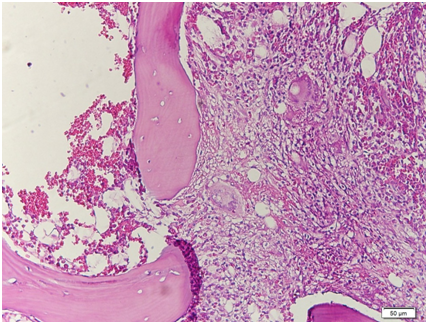

In Taiwan, Wang et al.7 studied 164 out of 3058 culture‒confirmed TB patients (5.4% prevalence) who fulfilled the criteria for disseminated tuberculosis from January 1995 to December 2004. 87 patients (53%) had underlying co‒morbid conditions such as AIDS, diabetes mellitus, malignancy, end‒stage renal disease, autoimmune disease, and alcoholism. Within one year of follow‒up, 99 (60.4%) patients were completely treated and 51 (31%) died, 10 (6.1%) were under treatment and 4 (2.4%) were lost. Poor prognosis factors reflect the severity of TB or the underlying diseases, and include albumin <3.5 g/dL, total bilirubin >1.0 mg/dL, creatinine >1.5 mg/dL and delayed anti‒tuberculosis treatment. This patient had positive AFB smears from all over her body (lungs, urine, stool, pelvis, bone marrow) – suggesting an immuno compromised state such as HIV/AIDS or a person with malignancy or diabetes mellitus. However, the result of HIV screening for this patient was nonreactive and her blood sugar levels were with normal limits. Patients with disseminated tuberculosis have varied presentations which may be lethal if detection is delayed, including pancytopenia,8 hemophagocytic syndrome,9,11 bone marrow necrosis,13 disseminated intravascular coagulation,10 isolated thrombocytopenia.14 Disseminated tuberculosis is treated with quadruple anti‒Koch’s medications, under the DOTS strategy. Interestingly, although the current recommendation is a six‒month treatment regimen for disseminated TB, patients with disseminated tuberculosis are treated for a minimum of 12 months in Saudi Arabia.15 The same is true for our section. However, anti‒tuberculosis medications do have its inherent risks and complications. Petechial rash may suggest thrombocytopenia in patients taking rifampicin.4 The platelet count was checked immediately in our patient and since it was initially low, rifampicin hypersensitivity was identified as the cause. The medications were stopped and hematologic disturbances were corrected prior to resuming the medications. The plan was to restart the medications one by one at intervals of 2‒3 days once the rash improved. However, since there was no observed improvement despite cessation of the medications, a primary hematologic disorder was considered (Figures 11‒14).

Figure 12 Scanning view: the bone marrow aspirate smear is cellular and polymorphous showing myeloid and mild increased in erythroid precursors in all stages of maturation with an M/S ratio of 1.2:1. No extraneous cells noted. Megakaryocytes are identified.

Figure 13 Low power view. The bone marrow core biopsy is hypercellular for age showing 80‒90% cellularity.

Figure 14 High‒power view. There is significant granuloma formation with Langhans type giant cell (arrows) focally scattered in the marrow matrix. The residual marrow shows erythrogranulopoiesis with maturation. Megakaryocytes are adequate.

A bone marrow aspirate and core biopsy was done in our patient primarily to rule out a hematologic disorder to explain the hematologic signs and symptoms of the patient. Several researches showed the utility of bone marrow aspirate and a blood culture to diagnose disseminated tuberculosis. Some investigators have used PCR to detect mycobacterial DNA in bone marrow smear and it is reported to be useful.15 Bone marrow aspiration however is an invasive procedure, and several studies show that blood culture compares to bone marrow biopsies in its yield to diagnosis disseminated tuberculosis. In the study by Crump & Reller,23 mycobacterial blood culture appeared to be as sensitive as bone marrow culture in diagnosing disseminated tuberculosis (sensitivity, 58% vs. 54%). Mycobacterial blood culture can play an increasing role in the diagnosis of disseminated tuberculosis when localized disease is not found. Comparing bone marrow biopsies with blood cultures in the recovery of mycobacteria in the diagnosis of disseminated tuberculosis, Pacios et al.24 noted that blood culture represent a more sensitive and less invasive alternative to bone marrow cultures, but provided no advantage for the diagnosis of disseminated mycobacterial infection caused by Mycobacterium tuberculosis.24 To diagnose disseminated tuberculosis, a search for sites of localized disease should be undertaken, and samples from these sites should be obtained. Examination of biopsy specimens from sites of localized disease, especially lymph nodes, has a high diagnostic yield, including bone marrow biopsies and blood culture. Combined mycobacterial culture and histopathologic examination of biopsy from bone marrow were more sensitive and faster than mycobacterial blood culture in diagnosing disseminated tuberculosis.